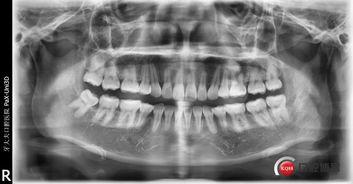

最近,网络上突然兴起了一股“成人模拟拔牙视频大全”的热潮。这些视频里,不仅有拔牙的过程,还有各种拔牙工具的展示,甚至还有拔牙后的护理方法。那么,这些视频究竟是从何而来,又为何会如此受欢迎呢?

据调查,这些视频大多来源于一些医学教育平台和口腔医院。它们旨在通过直观的方式,让更多人了解拔牙的过程,减少患者对拔牙的恐惧。当然,也有一些视频是由个人上传的,他们可能是口腔医学专业的学生,也可能是对拔牙感兴趣的人。

其次,这些视频以直观的方式展示了拔牙的全过程,让人们对拔牙有了更清晰的认识。以前,我们只能通过医生的解释来了解拔牙,而现在,我们可以直接通过视频来观察。